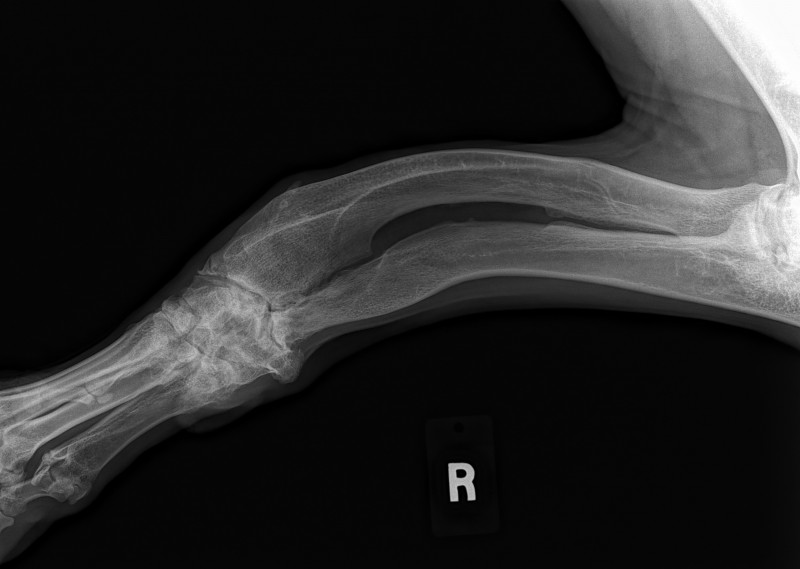

Sean has been diagnosed with a retro-peritoneal liposarcoma.

The current size of his mass is 8.2 cm x 10 cm x 21 cm. This is an extremely RARE cancer – less than 1%.

To further complicate matters, this mass has herniated down into his thigh and groin severely compromising his ureter and femoral nerve. He has had three CT scans of which his latest has shown that to date his chest remains clear of metastasis and his lymph nodes are not enlarged. His MRI has shown that his case is extremely complicated and the surgery he shall specifically require, scheduled for March 23rd has ONLY ever been done twice before by the two expert surgical oncologists assigned to him.